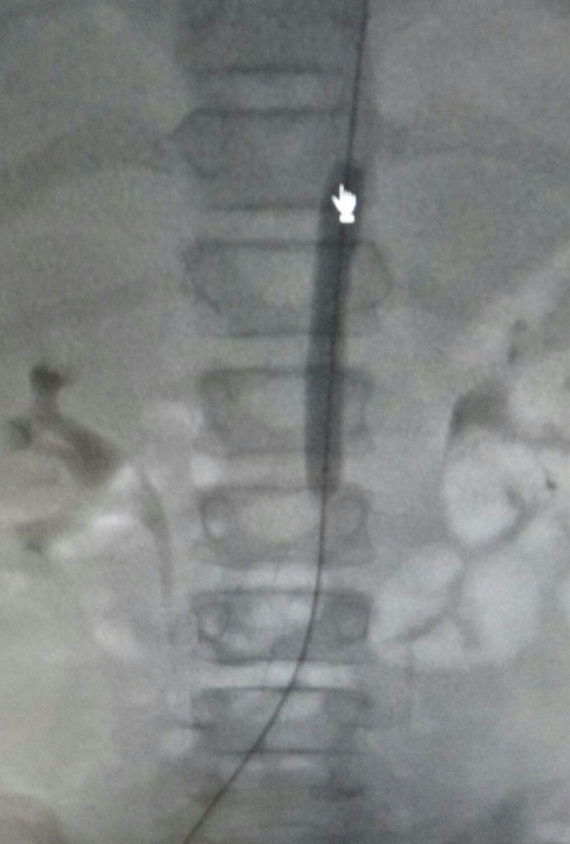

DIAGNÓSTICO FINAL: sindrome de aorta media

El síndrome de aorta media (SAM) consiste en una estenosis de la aorta abdominal generalmente con inclusión de las arterias renales y viscerales. Es un síndrome poco frecuente, aunque se considera una causa importante de hipertensión arterial (HTA) en niños y adolescentes. Se cree que su origen embriológico se debe a un fallo en la fusión de las dos aortas dorsales y la etiología es idiopática en un alto porcentaje. Su localización es interrenal en el 54% de los casos. Clínicamente cursa con HTA, sintomática o no. A la exploración puede apreciarse soplo abdominal, pulsos femorales disminuidos o ausentes y diferencia de TA entre miembros superiores e inferiores. El diagnóstico definitivo se alcanza por arteriografía y angio-RM, principalmente (2).